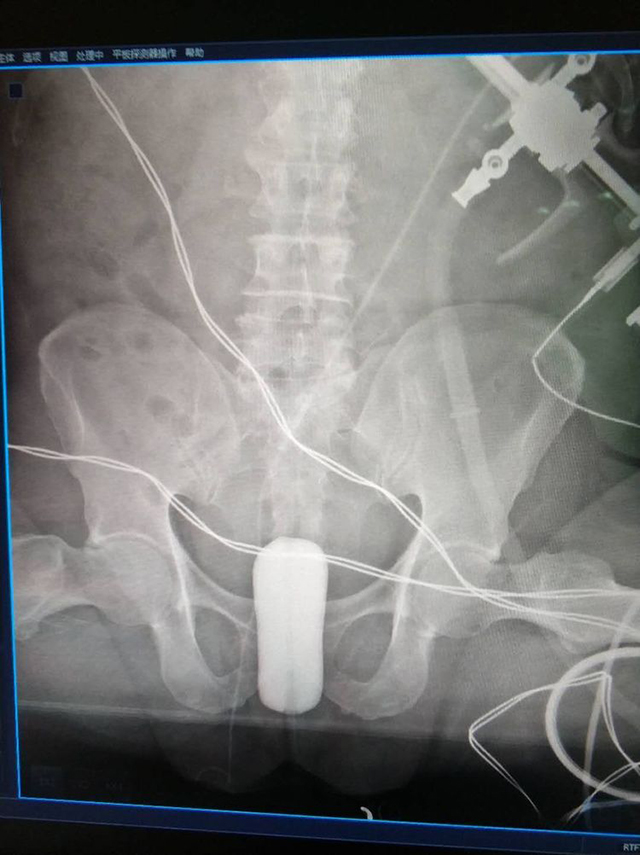

2018年1月16日浙江萧山医院范祎主任和周海永医师共同完成一例扩开术。患者73岁,前列腺43g,选用39B型号扩裂导管。术中扩开内外囊时加了10%的碘佛醇通过X线可以清楚看见扩开后水囊的位置,先内囊注水7ml,扩开前列腺尖部,再外囊注水70ml扩开12点,通过电切镜术后观察,扩开充分!尿道通畅!

▲内囊扩开造影

▲外囊扩开造影